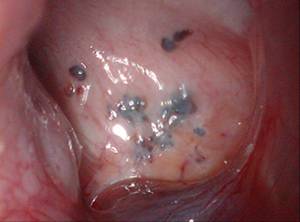

腹腔镜检查:目前内异症诊断的金标准,即腹腔镜下在盆腔腹膜上见到一些紫蓝色、暗红色或者白色的结节,需结合组织病理学结果,病灶中可见子宫内膜腺体和间质即可确诊(下图)。

图:腹腔镜下的内异症病灶